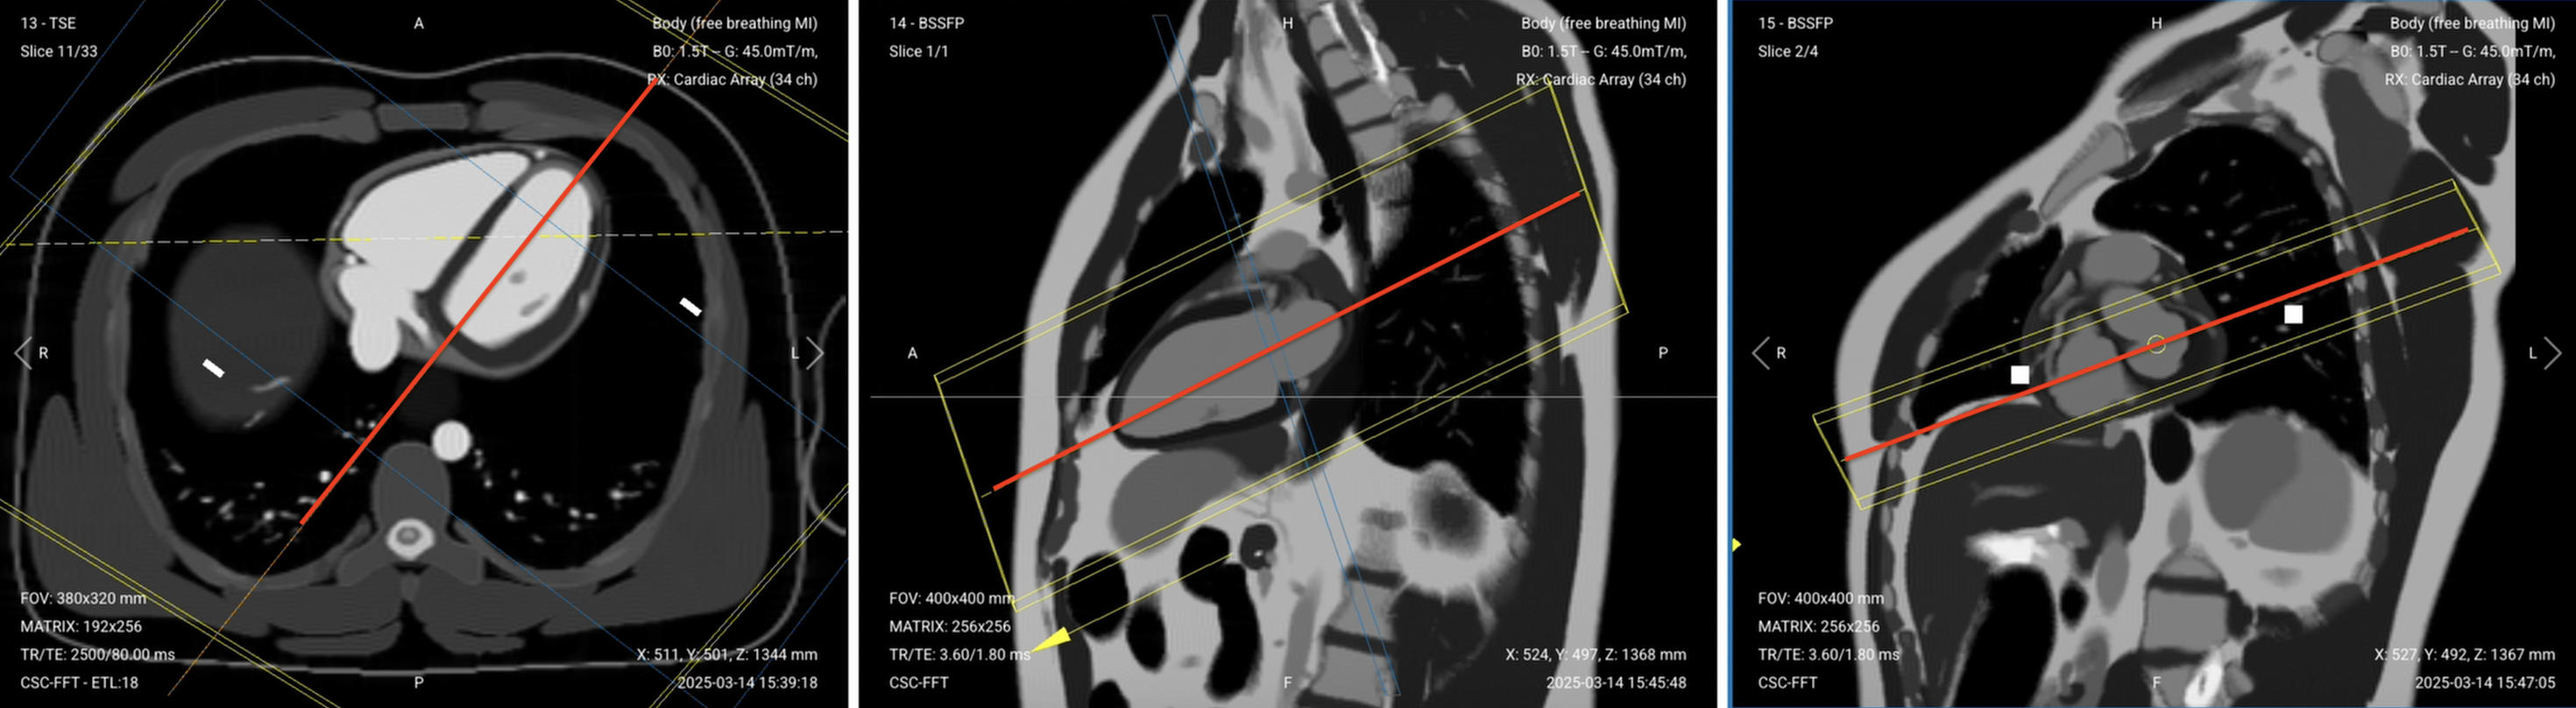

Correct Planning – TI Scout

Planning Instructions:

• Copy the slice geometry and planning from your previous SAX cine stack. Start by scrolling through the cine slices and select a mid-ventricular slice to copy; a slice that shows a full ring of myocardium.

• Use the left ventricle as your anatomical reference.

• In the long-axis view, center on the left ventricle at the papillary muscle level.

• Use appropriate geometry parameters:

• Slice number: 1 slice at mid-ventricular level.

• Slice thickness: 8 mm for good SNR during multiple TI sampling.

• Slice gap: Not applicable (single slice).

• Set the fold-over direction (phase encoding) to right–left (RL) to match short-axis orientation.